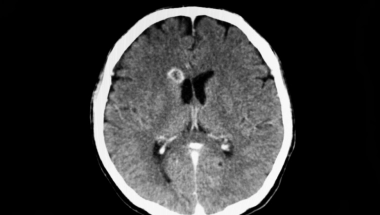

Nakon odrađenog skenera glave lekari su bili sigurni da žena boluje od tumora na mozgu jer su snimci pokazali leziju. Međutim, lumbalna punkcija pokazala je šokantnu dijagnozu - pacijentkinja je bila zaražena Balamuthia mandrillaris, jednoćelijskim organizmom koji se širi na mozak i ubija devet od 10 pacijenata.